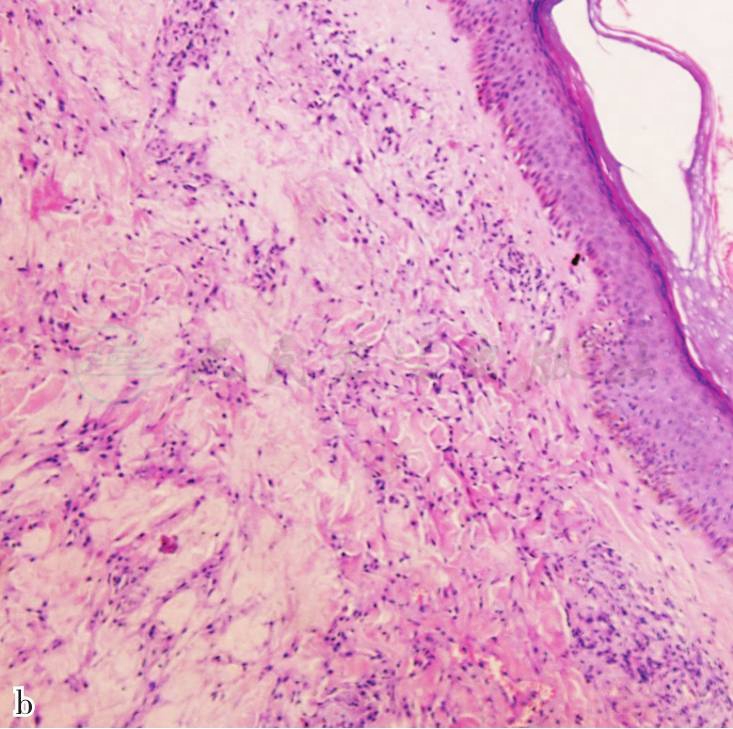

组织病理:表皮轻度角化亢进,真皮灶状胶原纤维变性,周围慢性炎细胞浸润,未见泡沫细胞(图3)。

图3 表皮轻度角化亢进,真皮灶状胶原纤维变性,周围慢性炎细胞浸润